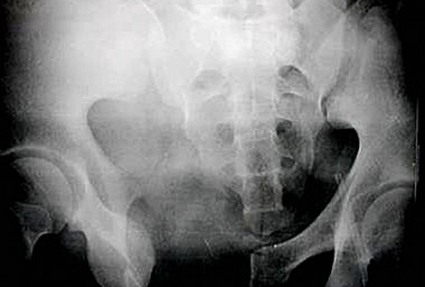

• Den vanligaste frakturtypen är lateralt kompressionsvåld. Skadan uppkommer genom våld utifrån direkt mot ena höftbenet eller via caput femoris, vilket ger upphov till inåtrotationsvåld av bäckenhalvan. Detta ses vid bl a trafikolyckor då patienten i egen bil blir påkörd från sidan. Oftast ses det dock som lågenergitrauma då en äldre patient faller i samma plan mot utsidan av sin höft (Figur 4, mitten).